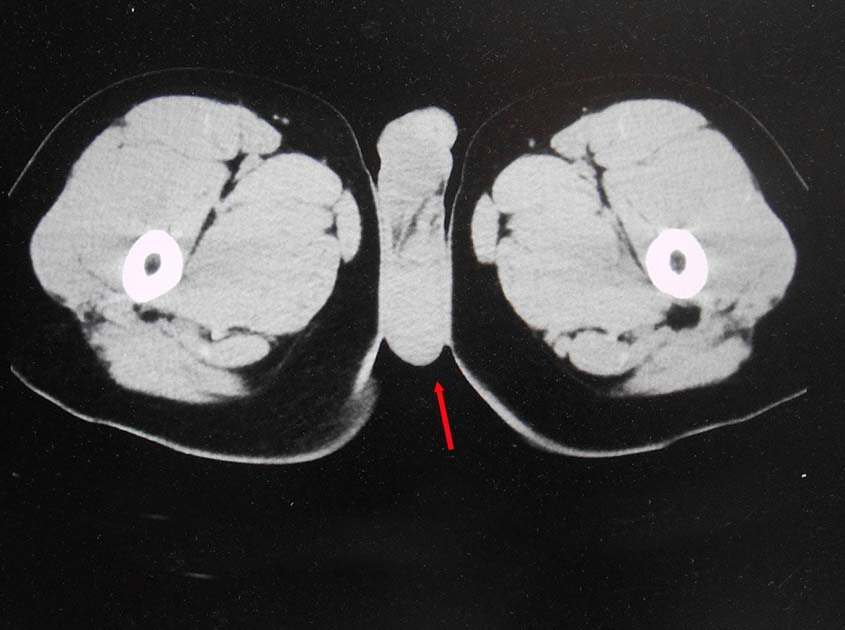

無痛性精巣腫大で泌尿器科受診. 画像診断では, 左精巣最大径4.5cmの腫瘤で縦隔リンパ節転移が疑われた. 左高位精巣摘除術をうける.

前縦隔や右心横隔膜角部に不定形, 不均一でべたっとした腫瘤状軟部濃度域を認める. 節外浸潤を伴ったリンパ節転移の可能性を考える.

画像: 左精巣腫瘤. 縦隔リンパ節転移疑い.